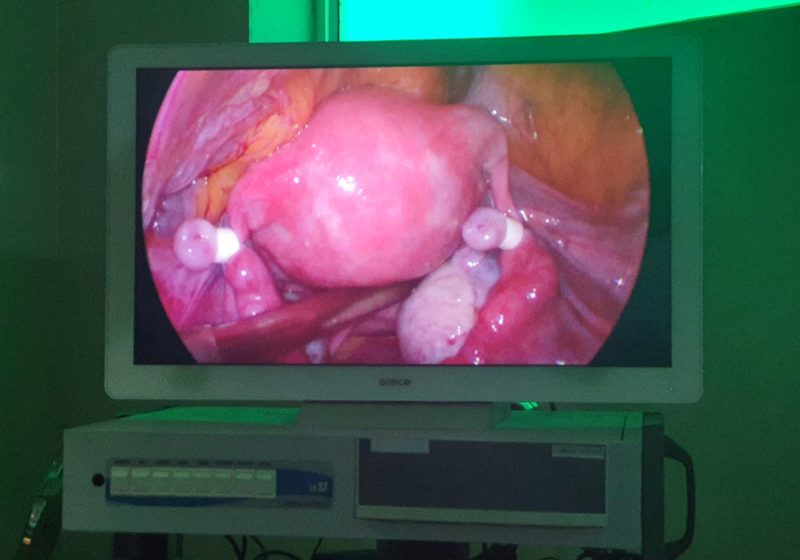

- Surgery procedures done at Spandana

- Tumors And Fibroids Surgically Removed In Spandana Hospital